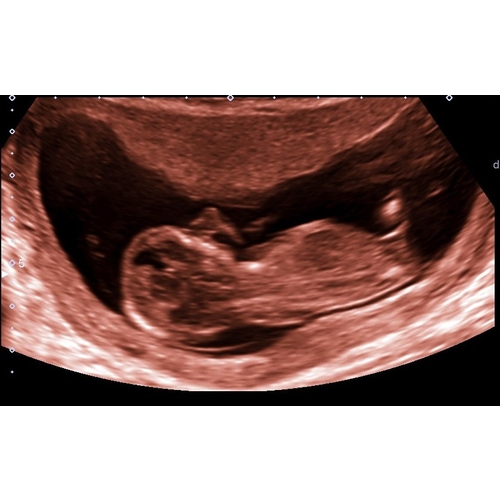

De nub, skull en ramzi theorie gaven allemaal aan dat we een meisje zouden krijgen. Toch hebben twee afzonderlijke echoscopisten gezien dat het een jongetje wordt 馃挋